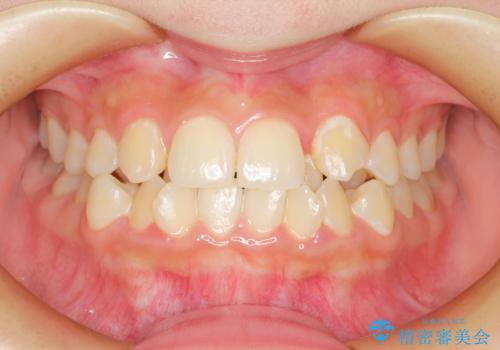

閉院による転院からのリカバリー。インビザラインからワイヤー矯正への切り替え

担当医 河口智英